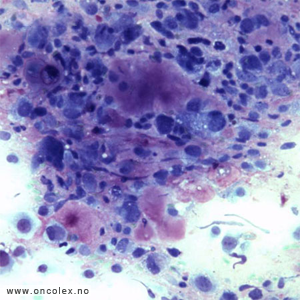

Osteosarkom er det vanligste sarkomet i ben. Mikroskopisk ses malignt utseende celler som produserer benvev eller osteoid. Det finnes mange subtyper. Klassifikasjon baseres på lokalisasjon i knokkelen og på kliniske, radiologiske og mikroskopiske funn.

Cytologisk bilde av osteoblastisk osteosarkom. |

Klassisk osteosarkom

Klassisk osteosarkom ses hos unge i alderen 10–30 og sitter i metafysen i lange rørknokler, typisk rundt kneet og øverst i overarmen. Tumor viser malignt utseende celler som produserer osteoid og ben med forkalkninger. Det kan i tillegg ofte påvises områder med kondroblastisk og/eller fibroblastisk utseende. Dersom man ikke får representativ biopsi kan man feilaktig stille diagnosen kondrosarkom eller fibrosarkom på et slikt materiale.